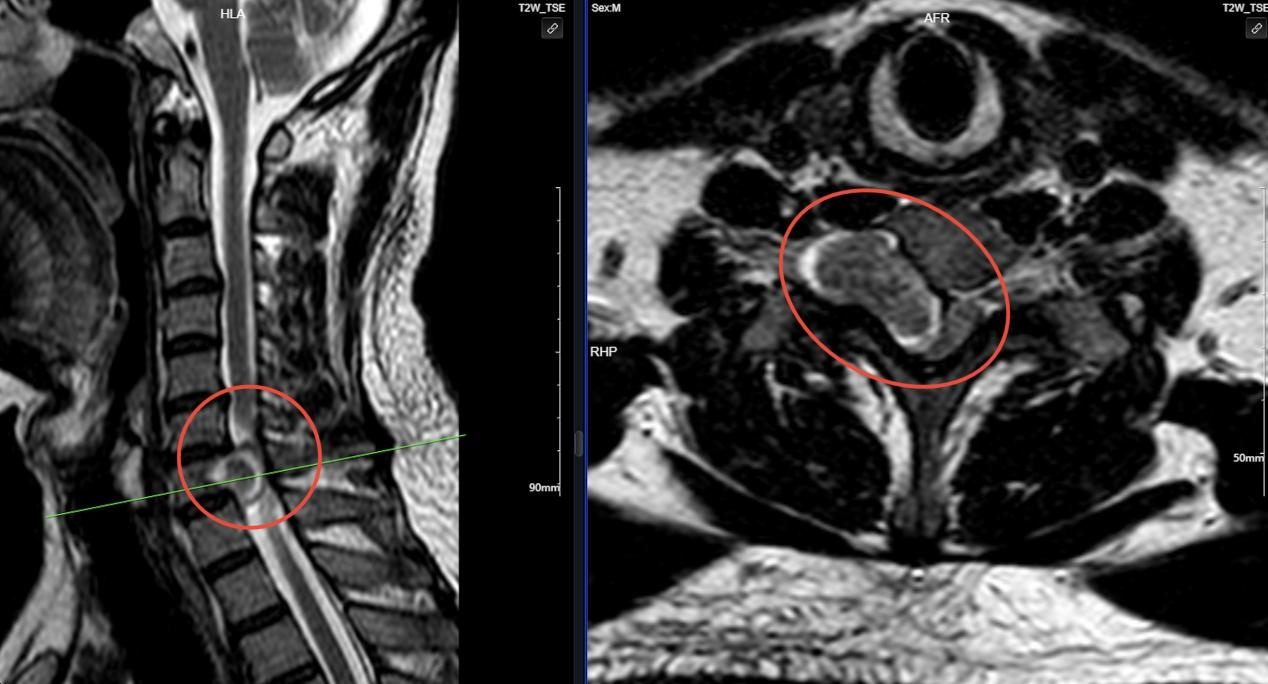

經疼痛科洪錦財副主任醫(yī)師詳細詢問病史、查體、影像學檢查后發(fā)現(xiàn),患者頸椎椎管內占位性病變,如不進行手術治療摘除腫瘤,隨著腫瘤的增大,頸脊髓將進一步受壓損傷,最終可能導致肢體癱瘓。

紅圈處磁共振提示:頸椎椎管內占位、脊髓神經受壓嚴重.jpg

磁共振提示:頸椎椎管內占位、脊髓神經受壓嚴重